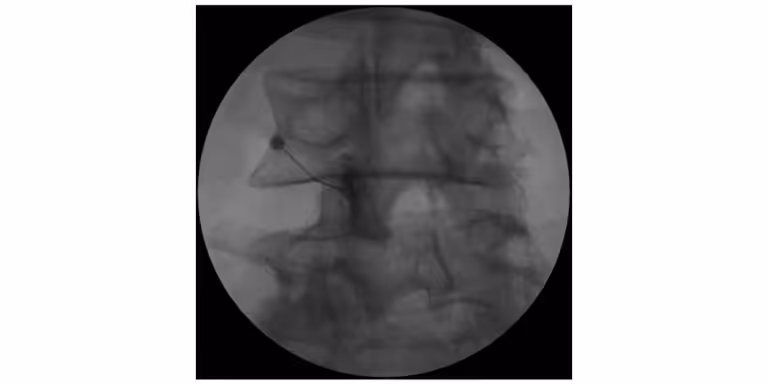

X-ray image showing the placement of a needle in the spine during a medical procedure.

Step 2: X-Ray Image Guidance

Medical image guidance (fluoroscopy/X-ray) is used to visualize the spine and guide the needle to the correct location near the facet joint.